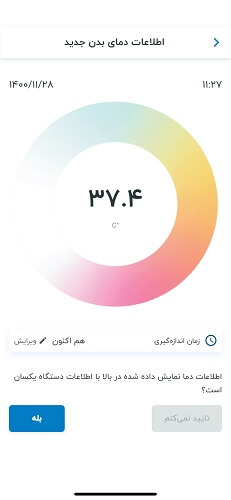

دماسنج هوشمند غیرتماسی آریو

اندازهگیری دقیق در کمتر از ۲ ثانیه، مطابق با استانداردهای اتحادیه اروپا.

اتصال به تلفن همراه از طریق بلوتوث